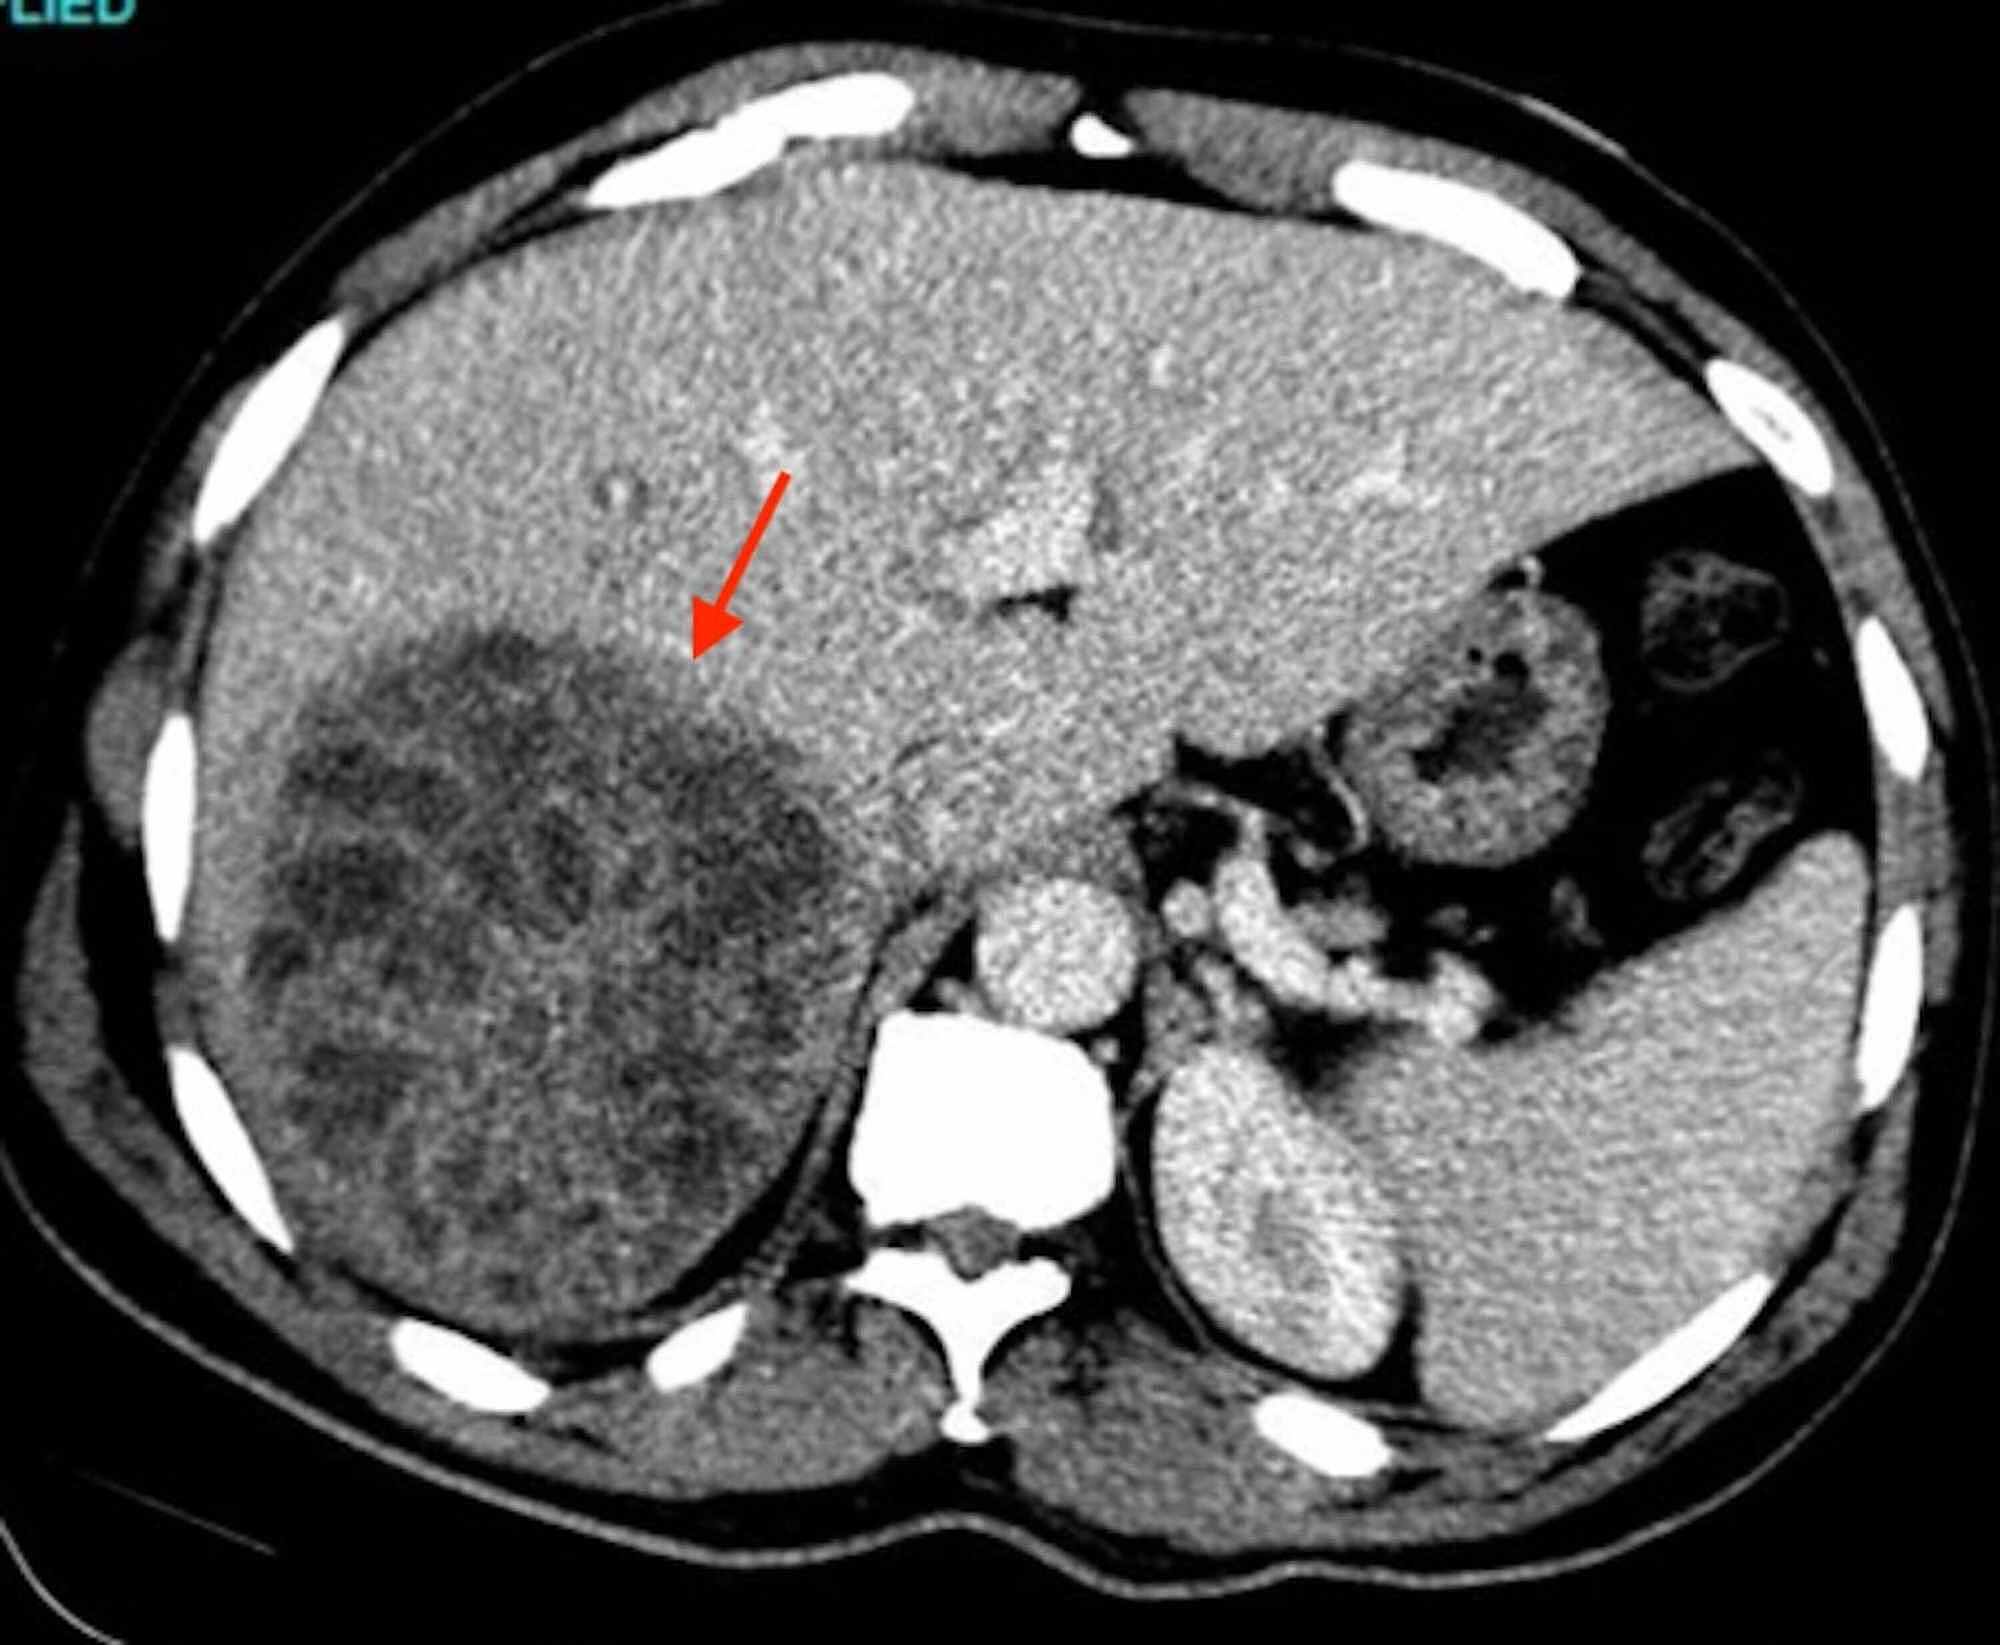

From www.semanticscholar.org

Figure 1 from Streptococcus mitis Abscesses Mimicking Liver Metastases Abscess From Strep The abscess can cause pain,. Medically, it is known as peritonsillar abscess. Group b strep (streptococcus) is a common bacterium often carried in the intestines or lower genital tract. An abscess is a collection of pus that forms near an area of infected skin or other soft tissue. Common for strep throat or pharyngitis) bacteria. An abscess in your throat. Abscess From Strep.

Figure 2 from Streptococcus mitis Abscesses Mimicking Liver Metastases Abscess From Strep Peritonsillar abscess is the most common deep infection of the head and neck, occurring primarily in young adults. The abscess can cause pain,. In general, peritonsillar abscesses take about 2 to 8 days to form and are normally caused by staphylococcus aureus (staph infection), haemophilus influenzae (pneumonia and meningitis) and group a hemolytic streptococci (gas; Group b strep (streptococcus) is. Abscess From Strep.